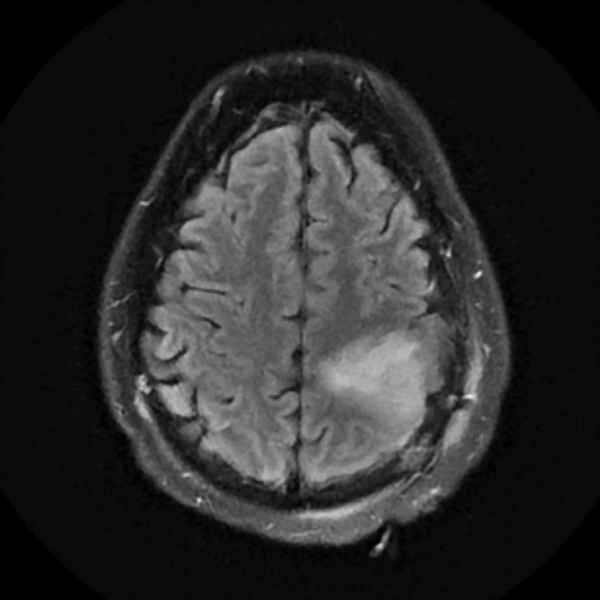

Treatment with chemotherapy and radiation under the care of Dr. Grewal resulted in a durable response of the tumor as evident in the post-treatment images.

The patient has returned to work with a resolution of cognitive impairment, has no neurological impairment, and the tumor continues to shrink on each serial MRI.

December 2019